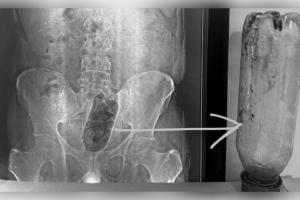

рмЖрмЧрнНрм░рм╛рм░рнЗ рмЖрм╢рнНрмЪрм░рнНрмпрнНрнЯрмЬрмирмХ рмШрмЯрмгрм╛: рмпрнБрммрмХрмЩрнНрмХ рморм│рмжрнНрн▒рм╛рм░рм░рнЗ рмлрм╕рм┐рм▓рм╛ рнз рм▓рм┐рмЯрм░ рмкрм╛рмгрм┐ рммрнЛрмдрм▓, рмЕрм╕рнНрмдрнНрм░рнЛрмкрмЪрм╛рм░ рмкрм░рнЗ рммрмЮрнНрмЪрм┐рм▓рм╛ рмЬрнАрммрми

рмЙрмдрнНрмдрм░рмкрнНрм░рмжрнЗрм╢рм░ рмЖрмЧрнНрм░рм╛рм░рнБ рмПрмХ рмЕрмнрм╛рммрмирнАрнЯ рмдрмерм╛ рмЖрм╢рнНрмЪрм░рнНрмпрнНрнЯрмЬрмирмХ рмШрмЯрмгрм╛ рм╕рм╛рморнНрмирм╛рмХрнБ рмЖрм╕рм┐рмЫрм┐ред рмПрмарм╛рм░рнЗ рмЬрмгрнЗ рнйрно рммрм░рнНрм╖рнАрнЯ рммрм┐рммрм╛рм╣рм┐рмд рмпрнБрммрмХ рмирм┐рмЬ рморм│рмжрнНрн▒рм╛рм░рм░рнЗ рмПрмХ рнз рм▓рм┐рмЯрм░ рмкрнНрм▓рм╛рм╖рнНрмЯрм┐рмХ рмкрм╛рмгрм┐ рммрнЛрмдрм▓ рмкрнВрм░рм╛рмЗ рмжрнЗрмЗрмерм┐рм▓рнЗ, рмпрм╛рм╣рм╛рмХрм┐ рмдрм╛рмЩрнНрмХ рморм│рм╛рм╢рнЯрм░рнЗ рмлрм╕рм┐ рмпрм╛рмЗрмерм┐рм▓рм╛ред рмкрнНрм░рм╛рнЯ рнйрнм рмШрмгрнНрмЯрм╛ рмзрм░рм┐ рмЕрм╕рм╣рнНрнЯ рмпрмирнНрмдрнНрм░рмгрм╛ рмнрнЛрмЧрм┐рммрм╛ рмкрм░рнЗ рмкрм░рм┐рммрм╛рм░...